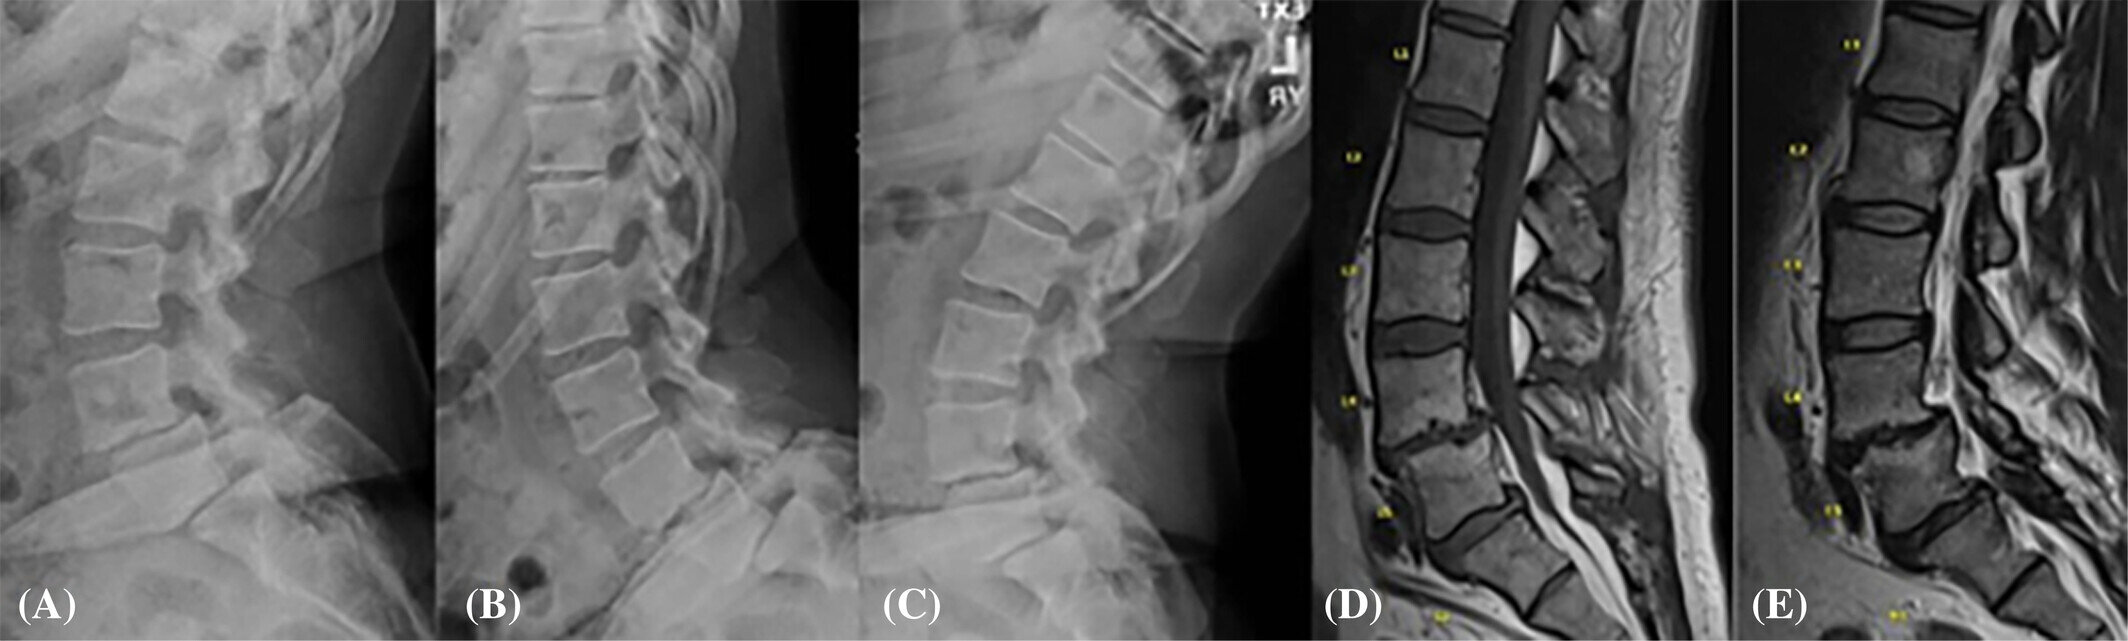

В рамках нового исследования специалисты наблюдали за пациентами с поясничным дегенеративным спондилолистезом и без него. Они хотели понять, есть ли разница в микробиоме кишечника этих людей.

В новом исследовании приняли участие 33 человека старше 50 лет. 12 из них не имели поясничного дегенеративного спондилолистеза, а у 21 он был. У людей, страдающих этим заболеванием, были обнаружены более высокие уровни провоспалительных (вызывающих воспаление) бактерий в кишечнике.